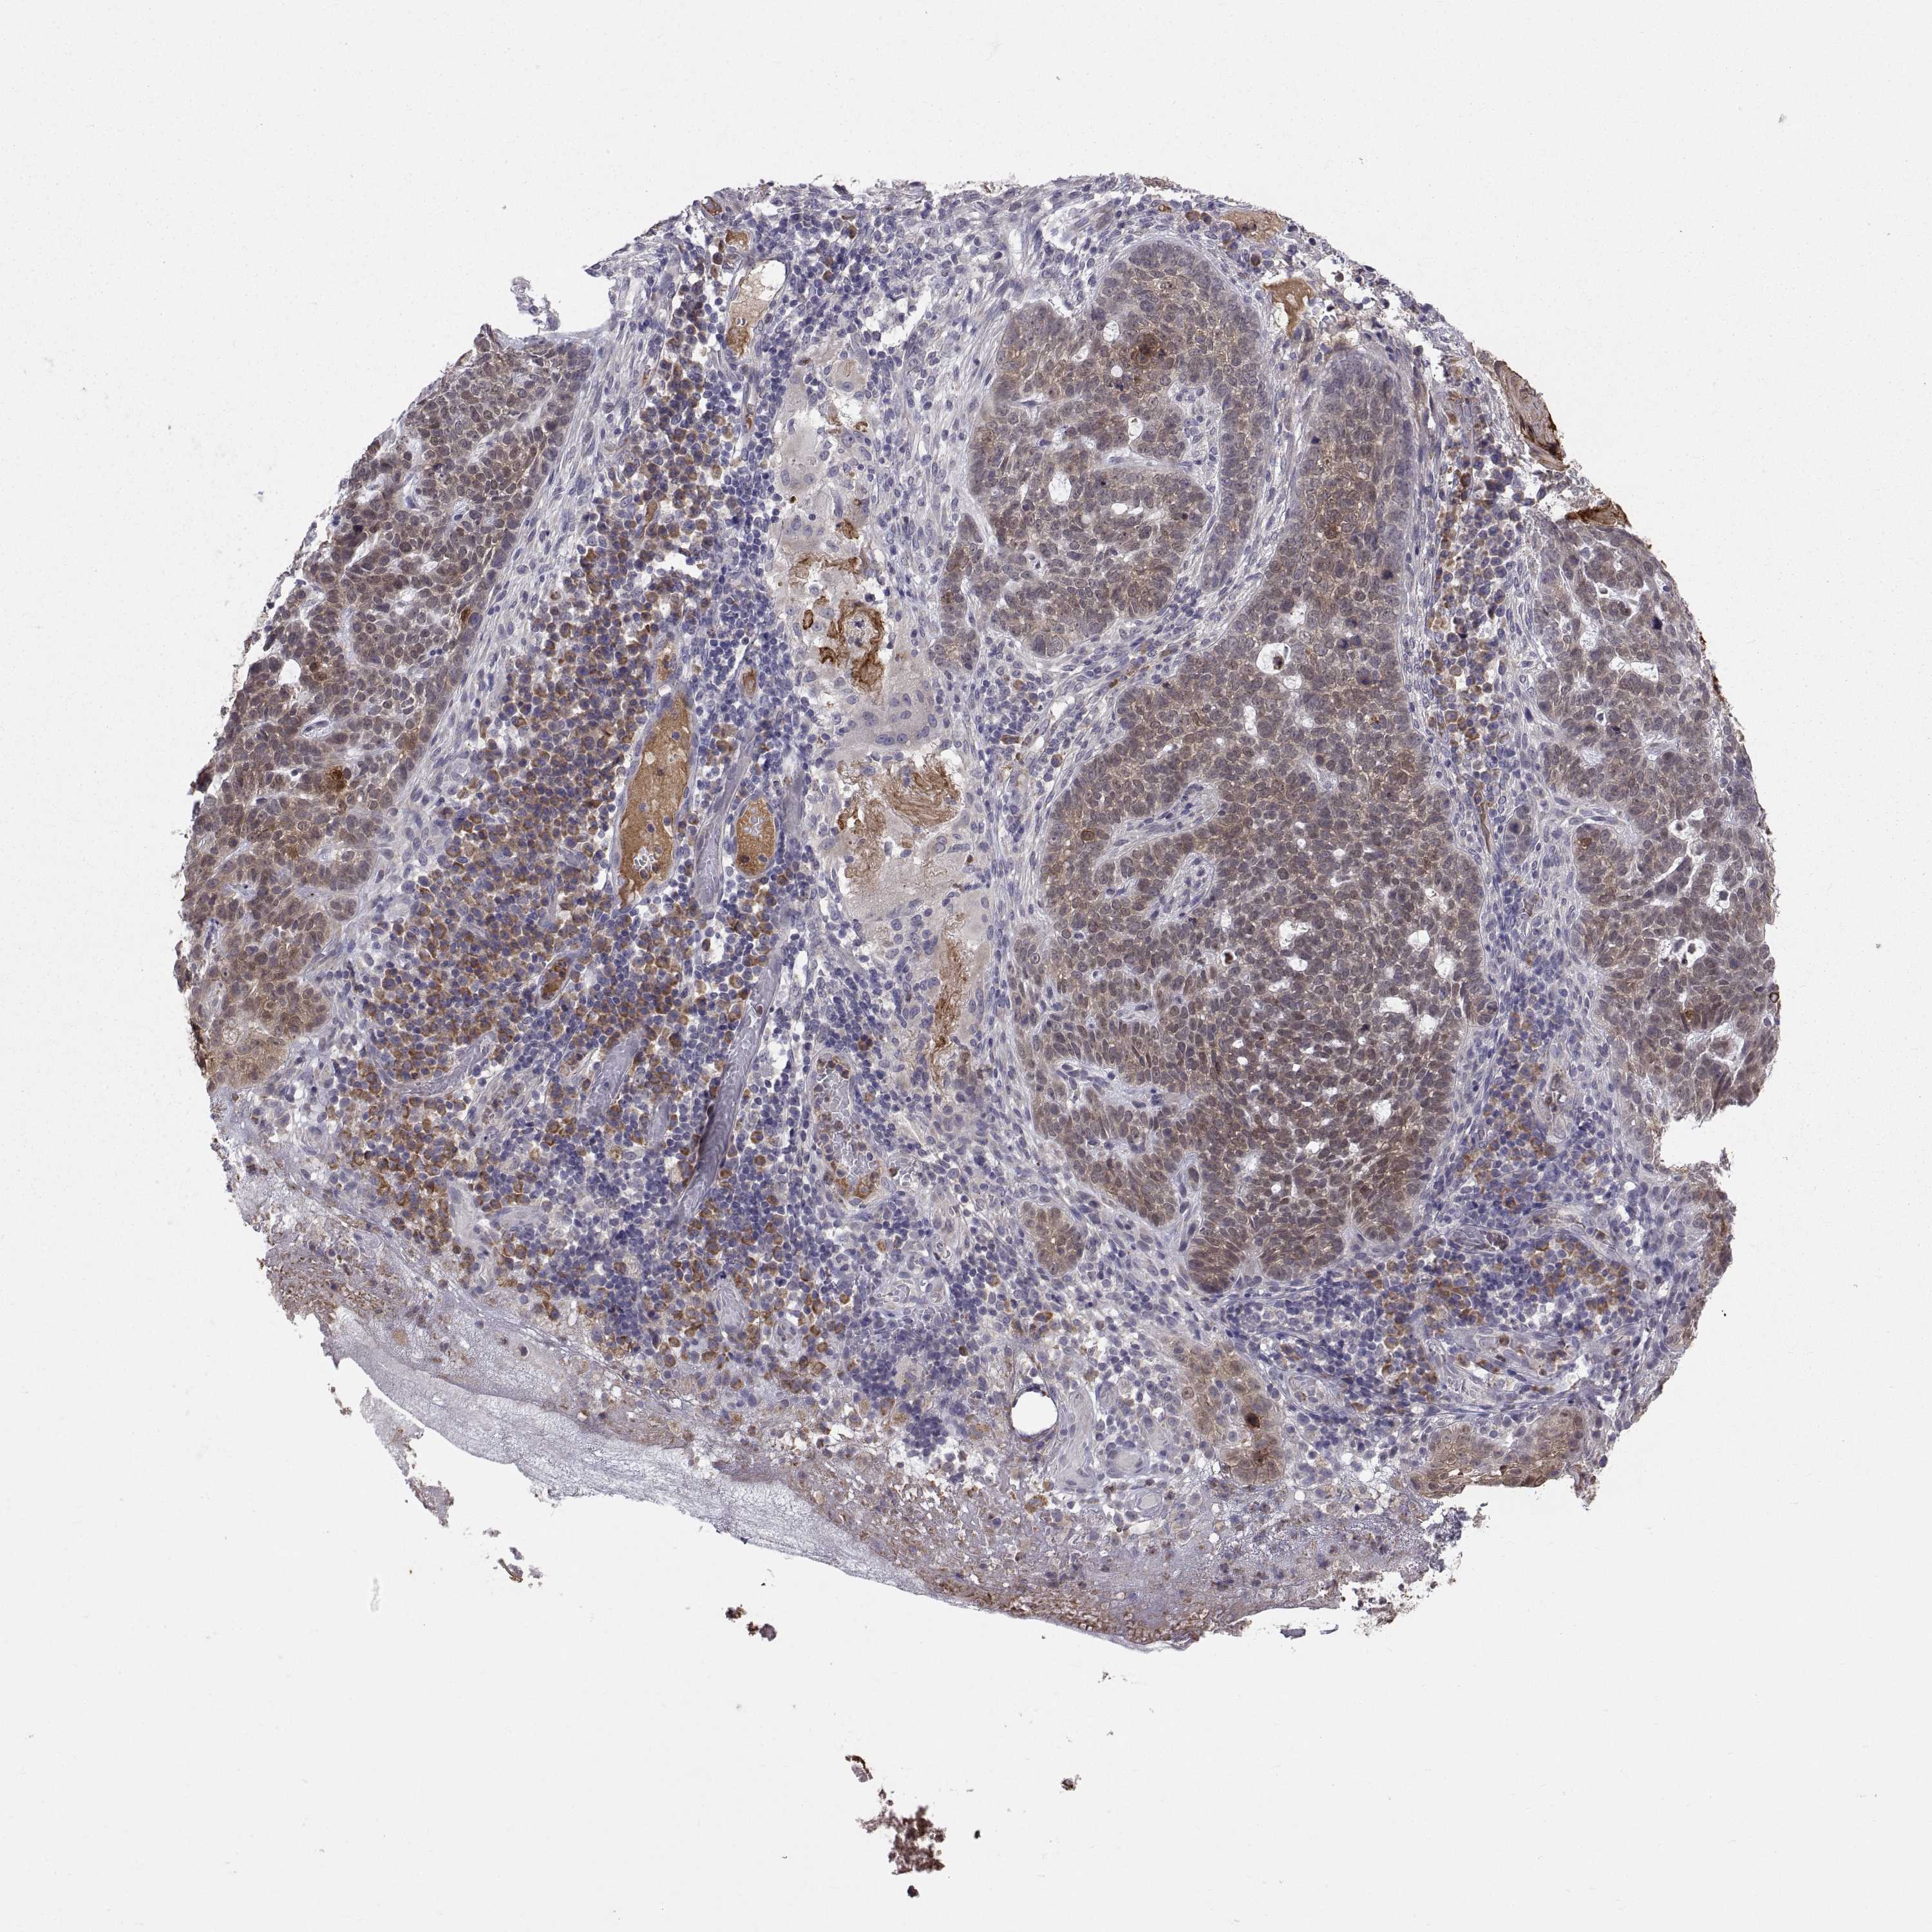

SKIN CANCER - Protein expressioni

A mouse-over function shows sample information and annotation data. Click on an image to view it in a full screen mode. Samples can be filtered based on level of antibody staining by selecting one or several of the following categories: high, medium, low and not detected. The assay and annotation is described here.

Each image is clickable and will lead to virtual microscopy that enables deeper exploration of all samples and also displays staining intensity scores, fraction scores and subcellular localization as well as patient and tissue information for each sample.

Antibody HPA027221

Basal cell carcinoma

Squamous cell carcinoma, NOS